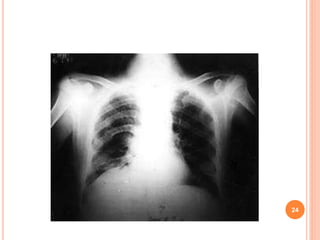

Chest X-ray : There are no diagnostic

features of asthma on the chest X-ray

A chest X-ray may be helpful in excluding

a pneumothorax, which can occur as a

complication of asthma